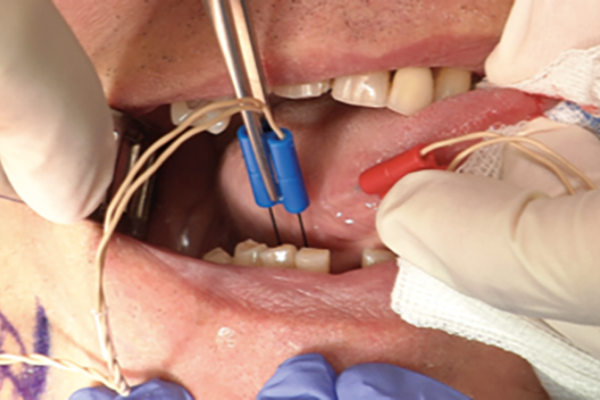

Sialendoscopy